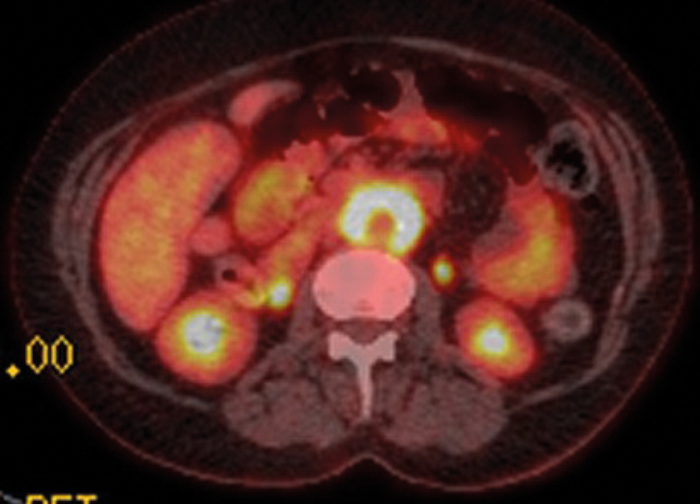

Figure 5: Axial fused PET-CT shows extensive uptake and metabolic activity encasing the aorta.

PET-CT with 18F-fluorodeoxyglucose (18F-FDG) can be used to ascertain if there is functional tissue with areas of increased glucose activity. Active RPF is seen as an area of increased uptake (Figures 5 and 6) and this can be used to assess if treatment has been successful. Uptake is seen in active inflammation but not if there is metabolically inactive disease [5]. However, lymphoma also demonstrates avid 18F-FDG uptake, so PET-CT cannot give a definitive diagnosis, but needs to be interpreted in conjunction with other imaging modalities.